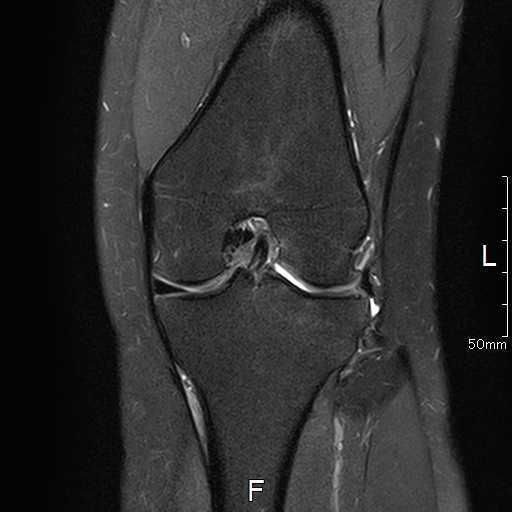

MRI所見

| 手術前 | 手術後 |

![]() ![]() | ![]() ![]() |

| 関節水腫、骨髄浮腫を認める | 術前認めた水腫などの所見はなし |